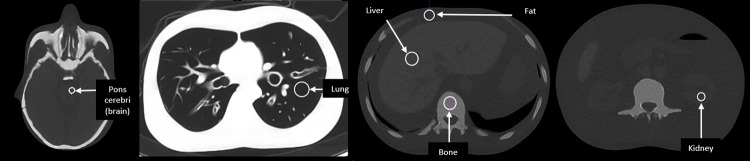

Materials and methods: A whole-body CT phantom was scanned with standard filtration in CRS protocols, using 120 kV with 20mAs-ref for bone L/C (used in 18F-Sodium Fluoride (NaF) PET-CT) and 40mAs-ref for soft tissue L/C (used in 18F-Fluorodeoxyglucose (FDG) PET-CT), followed by tin filter scans at 100 kV (Sn100kV) and 140 kV (Sn140kV) with a range of mAs settings. For each scan, effective dose (ED) in an equivalent-sized patient was calculated, and image quality determined in 5 different tissues through quantitative (contrast-to-noise ratio) and qualitative (visual) analyses. The relative dose reductions which could be achieved with the tin filter for comparable image quality to CRS images were calculated.